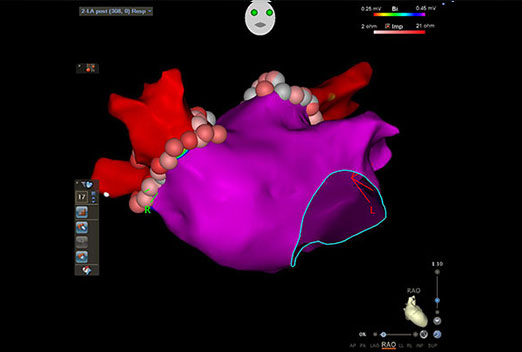

We have a some latest projects photos and Videos. this gallery explain different

health issues related to heart and more information for heart patients thats ill we help for your health improve.